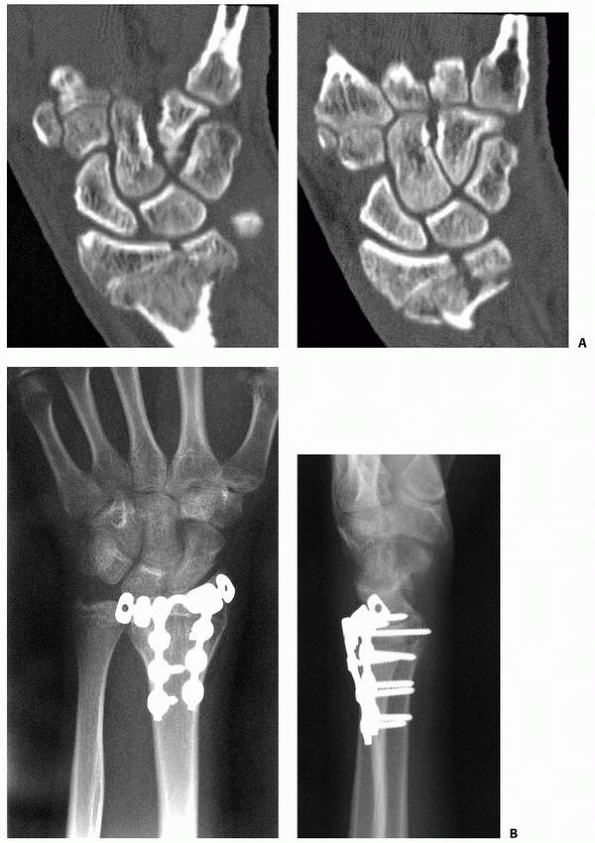

![]() |

FIGURE 9-21 A. CT scan of displaced Salter-Harris type IV fracture. B. Surgical correction included external fixation distraction, arthroscopically assisted reduction, and smooth pin fixation.